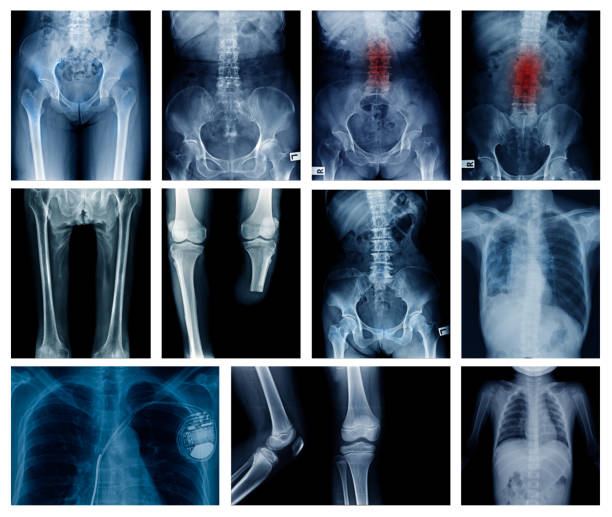

An expert in treating children with diseases and ailments of the brain and neurological system, particularly those affecting the spinal cord, nerves, muscles, and associated blood vessels, is known as a paediatric neurosurgeon. Brain tumours, seizure disorders, head and spinal malformations, and other ailments are all diagnosed and treated by paediatric neurosurgeons. We have the best doctor for pediatric spine surgery in santacruz who says The general status of your brain and nervous system can be monitored by your child's paediatrician or primary care physician, who can also treat some disorders, such as mild head traumas. When their primary care physician discovers or detects a more serious disease or condition of the brain or nervous system, such as scoliosis, hydrocephalus, or a brain tumour, many children consult a paediatric neurosurgeon for the first time.

The paediatric neurosurgery team has a lot of expertise taking care of kids with major nervous system disorders for which surgery is the recommended course of action. The most cutting-edge tools and methods are available to this team, including foetal surgery, intraoperative MRI, minimally invasive surgery using endoscope, and a specific kind of laser that uses heat to destroy tumours. From babies to teenagers, a paediatric neurosurgeon can take care of your child's medical needs. For instance, some newborns have birth defects known as neurological disorders. Children can occasionally experience strokes. This issue is dealt with in paediatric neurosurgery. Children with nervous system abnormalities are evaluated, diagnosed, treated surgically and non-surgically, given critical care, and given therapy in paediatric neurosurgery. Our doctor apurva prasad who is one of the best doctor for pediatric spine surgery in santacruz also says that A paediatric neurosurgeon is the expert with the skills and credentials to treat a kid who has issues with the head, spine, or nervous system. Pediatric neurosurgeons handle neurological conditions that are very different from those that adult or general neurosurgeons treat.

Why spine surgery required by some childrens